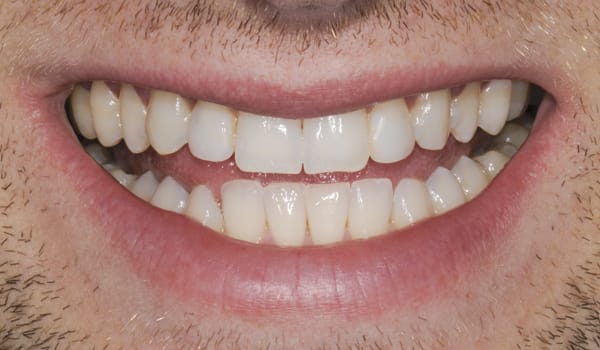

Four months postoperatively, it was observed the provisional restorations provided an excellent soft-tissue response, stable interproximal papillae, and evidence of maintaining the same gingival height (Figure 5 through Figure 7).

Both provisional restorations were removed, the definitive abutments were connected, and the abutment screws were torqued to 35 Ncm. The accuracy of the abutment margins at the gingival level, as transferred from the original custom scan body, is demonstrated in Figure 24. A cotton pellet and elastic, single-component, light-cured resin was placed to close the abutment access hole and light cured. The definitive restorations were cemented with radiopaque glass ionomer luting cement (Figure 25 through Figure 29).